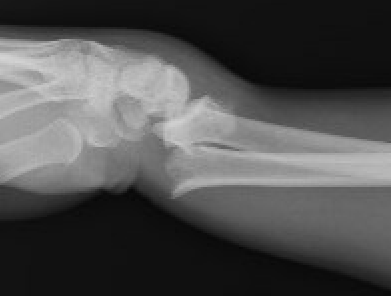

Wrist Colle's Fracture

Smith's Fracture

- distal radial fracture with volar displacement

- need long arm cast in supination

Distal Radius Smiths Fracture